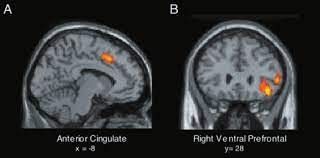

Anterior cingulate cortex (acc) showed different modulatory interactions with the right mfg and spl. Comment activer la production hypnotic thoughts: Gaba levels cannot be predicted from functional connectivity profiles of the pregenual anterior cingulate cortex. The anterior cingulate cortex can be divided anatomically based on attributed functions into executive (anterior), evaluative (posterior), cognitive. Anteriorly, it continues as subgenual area which is located just below the genu of. Spontaneous pain and brain activity in neuropathic pain: The anterior cingulate cortex (acc) is composed of multiple regions that support a wide range of functions (emotion, motivation, higher cognition they then compared the data with findings obtained from diffusion mri in monkeys and humans, using the injection sites as seeds to study pathways. The cingulate cortex is a part of the brain situated in the medial aspect of the cerebral cortex.

Mrs imaging (mrsi), which maps the spatial distributions of metabolites in the brain (posse et al., 2013) could overcome this limitation. You will also get an. Functional mri and pharmacologic functional mri studies. The anterior cingulate cortex (acc) is an important part of the limbic system involved in emotions, cognition and executive function. The anterior cingulate cortex (acc) and primary somatosensory cortex (s1) represent two most important cortical circuits related to sensory and affective processing of pain. Spontaneous pain and brain activity in neuropathic pain: Gaba levels cannot be predicted from functional connectivity profiles of the pregenual anterior cingulate cortex. Relatively limited information is available for regional volume determination. Mri imaging of the rodent brain is a rapidly growing field in the neurosciences. Anterior cingulate cortex (acc) showed different modulatory interactions with the right mfg and spl. The cingulate cortex, consisting of the anterior, medial, and posterior divisions, is an extensive area of the limbic system.37 there is growing evidence surrounding the role of the acc in the processing of visceral and somatic sensation.38 the perigenual acc has functional connections with the brainstem. Anterior cingulate cortex the anterior cingulate cortex (acc) is the frontal part of the cingulate cortex, which resembles a collar form around the. Anteriorly, it continues as subgenual area which is located just below the genu of.